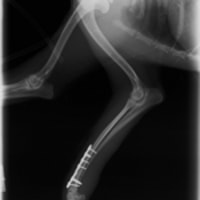

症例3:キルシュナーワイヤーのピンニングによる整復

ペルシャ猫 11ヶ月齢 雄

他院にて左大腿骨遠位の成長板骨折(salter-harrisⅠ型)が認められており、治療相談を目的として来院。当院にて、キルシュナーワイヤーを用いたピンニングにより骨折部位の整復を行いました。術後の経過は良好で、現在も経過観察中です。

術前レントゲン

術後レントゲン

機器

Arthrex社のターゲティングデバイスを用いてピンニングの位置を調整することで、確実な固定を行っています。当院ではこの手術器具以外にも、人の手術にも使用される様々な器具を導入し、手術精度を高め、また医療メーカーと新しい器具の開発、試作にも取り組んでおります。